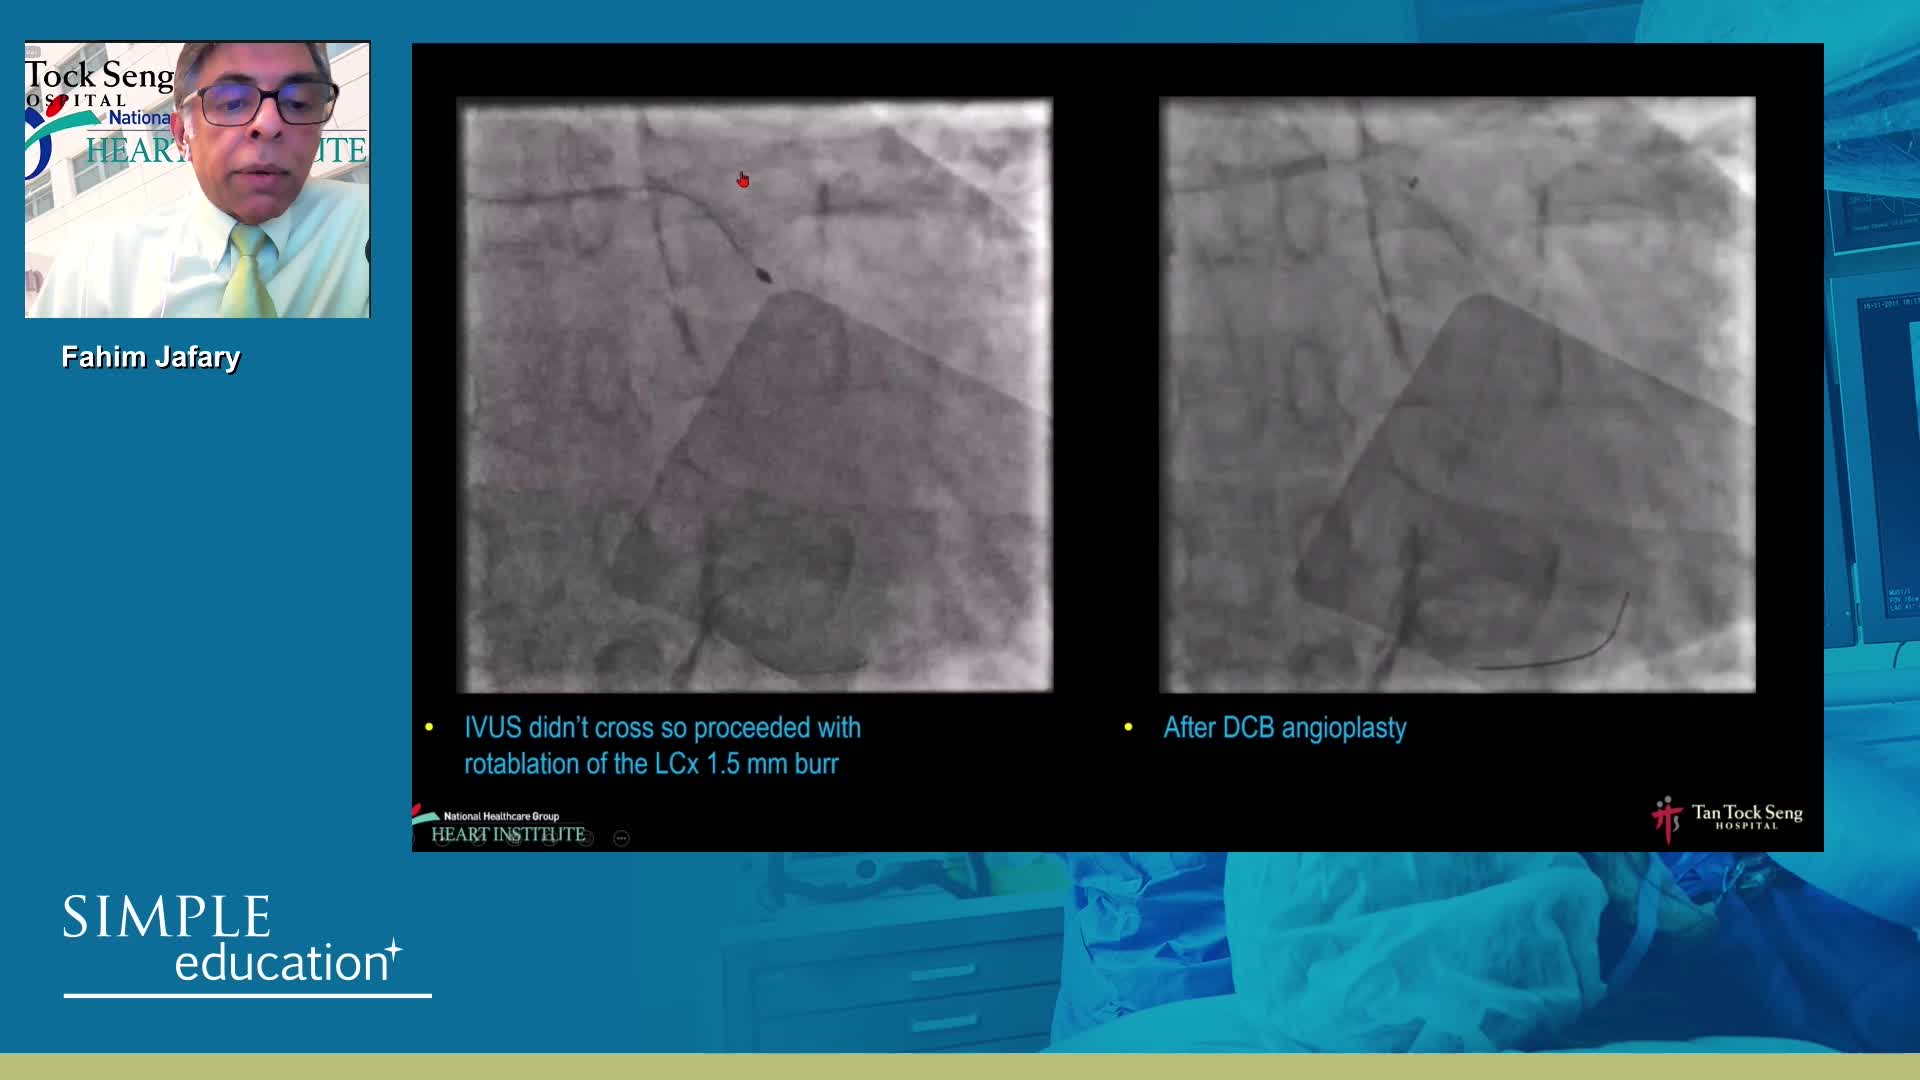

Intracoronary guidance in acute coronary syndromes - Dr Hernan Mejia-Renteria

Coronary Bifurcations: An Update on Diagnosis, PCI planning and Imaging and PhysiologyGuidance - Dr Dejan Milasinovic

Essential Guide to Intra-coronary Imaging for the General Cardiologist - Dr. Iqbal Malik